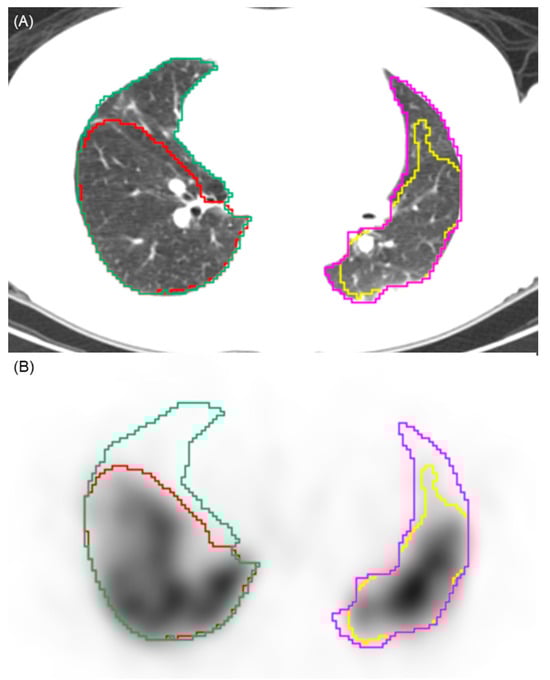

To determine perfusion defects on SPECT/CT images, each decile value was applied as a threshold. Voxels with counts below the selected threshold were defined as perfusion defects, whereas those above the threshold were considered to represent normal perfusion (Figure 1). The perfusion defect fraction was then quantified under each threshold condition to assess its variation between groups and was calculated as the perfusion defect volumes of both lungs divided by the total lung volume of both lungs. The 10% threshold was pre-specified as the primary analysis parameter. This selection was based on the clinical practice for high sensitivity in screening for CTEPH [4]. Thresholds ranging from 20% to 90% were evaluated as an exploratory analysis.

Figure 1.

Illustration of the automated segmentation process. (A) Axial CT image showing the automated segmentation of the right (green contour) and left (pink contour) lung parenchyma. (B) Corresponding SPECT image demonstrating the application of a 10% perfusion count threshold. Voxels with counts above this threshold are segmented (yellow and red contours), while areas below this threshold are identified as perfusion defects. This visualizes the volumetric quantification methodology used to calculate the perfusion defect fraction.